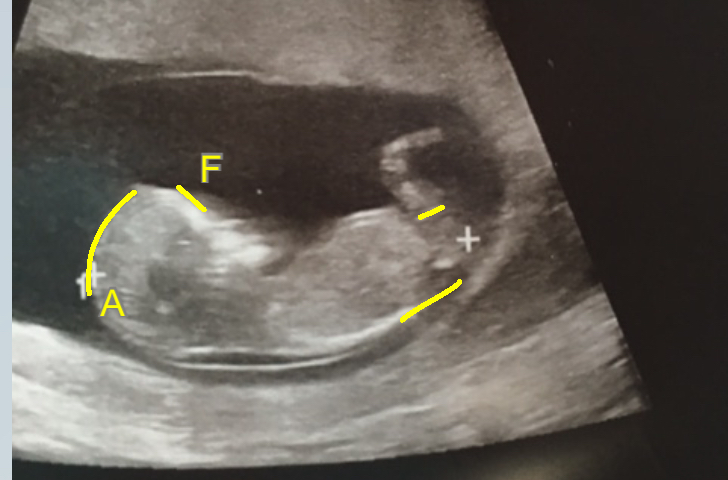

Any Guesses 11w6d